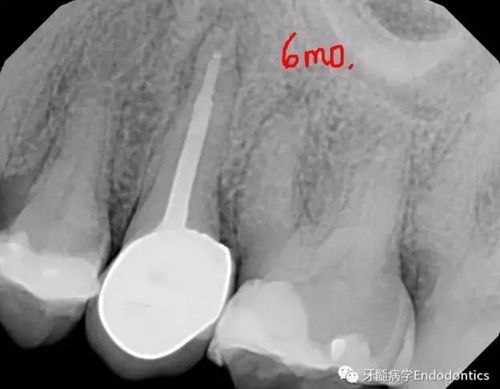

圖4.術(shù)后6個(gè)月